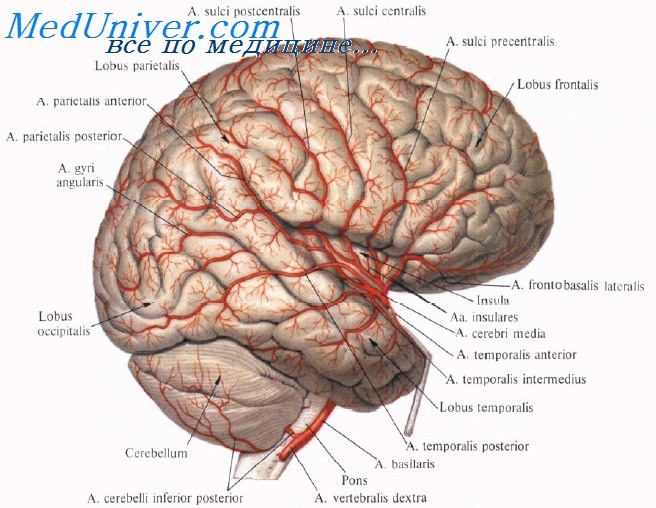

Анатомические снимки верхнелатеральной поверхности головного мозга